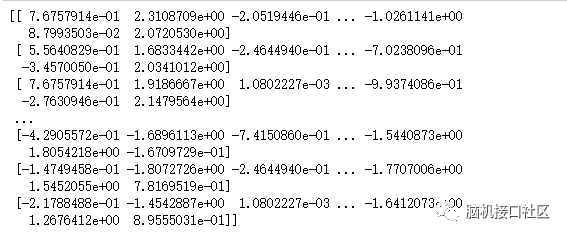

"""

利用 nilearn.input_data.NiftiMasker来提取mask上的fMRI数据,

并将其转换为数据序列

"""

from nilearn.input_data import NiftiMasker

masker = NiftiMasker(mask_img=mask_filename, standardize=True)

# 根据 filename检索二维数据

fmri_masked = masker.fit_transform(fmri_filename)

# 打印frmi_masked

print(fmri_masked)

# 查看其形状

print(fmri_masked.shape)(1452, 464)